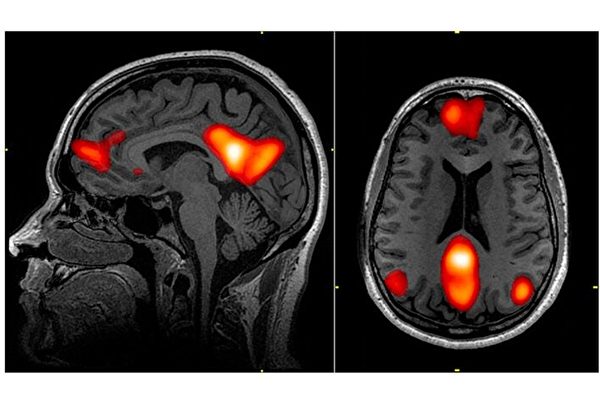

研究者让受试者欣赏画作、建筑或自然风光的图片,并用功能性磁振成像(fMRI)监控受试者脑部的活动。结果显示,受试者的大脑视觉区域对于不同类别的美图,产生的信号各不相同。然而在大脑中一个被称为“预设模式网络”(DMN,Default Mode Network)的功能性区域,却对所有类型的美图有着一致的脑部活动模式。

人们的心理活动、沉思,包括自我幻想都来源于这个“预设模式网络”。一般而言,预设模式网络在人的注意力没有放在外在的世界时开始运作,此时大脑会处在清醒的休息状态,例如做白日梦或放空时。人在想着自己或他人,回忆往事或计划着将来时,预设模式网络也会处在活跃的状态。也就是当人放空的时候,预设模式网络就会自然启动。

新的研究发现,这个网络在人们的审美、或被视觉艺术感动的体验中起着重要作用。研究者称,由于此网络当人与外在世界互动时处于休眠状态,因此视觉的美感体验信息出现在这个区域着实不同寻常。